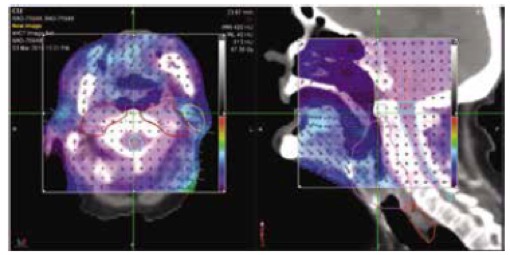

PreciseRTX™ - Για την ασφαλή χορήγηση θεραπείας σε περίπτωση επανακτινοβόλησης

Στην περίπτωση επανακτινοβόλησης, το σύστημα PrecisionRTX επιτρέπει την εισαγωγή των δεδομένων από προηγούμενες θεραπείες και την ενσωμάτωση τους στο νέο πλάνο ακτινοθεραπείας.

Σε συνδυασμό με την ικανότητα του συστήματος TomoTherapy να δημιουργεί σύμμορφα πλάνα αποφεύγοντας κρίσιμα όργανα, το σύστημα PreciseRTX™ δίνει την δυνατότητα στους ακτινοθεραπευτές Ιατρούς να προσφέρουν ασφαλείς θεραπείες στους ασθενείς που έχουν λάβει προηγούμενες θεραπείες με ακτινοβολία

PreciseRTX

- Επιτρέπει την εισαγωγή προηγούμενων πλάνων θεραπείας ασθενών από οποιαδήποτε άλλο σύστημα.

- Αποτελεί μια ενσωματωμένη λύση στο σύστημα σχεδιασμού θεραπείας Precision η οποία εξαλείφει την ανάγκη μεταφοράς δεδομένων μεταξύ συστημάτων διαφορετικών κατασκευαστών.

- Ευθυγραμμίζει αυτόματα τα απεικονιστικά δεδομένα και τα δεδομένα των πλάνων θεραπείας (σχεδιασμένες δομές και δοσιμετρικές κατανομές) προηγούμενων θεραπειών με τις νέες εικόνες αξονικής τομογραφίας λαμβάνοντας υπόψη μεταβολές στην ανατομία του ασθενούς (Deformable registration)

- Αθροίζει τις κατανομές δόσης των προηγούμενων θεραπειών με την κατανομή δόσης του νέου πλάνου θεραπείας.

- Περιλαμβάνει εργαλεία αξιολόγησης των συνολικών και των επιμέρους δοσιμετρικών κατανομών.